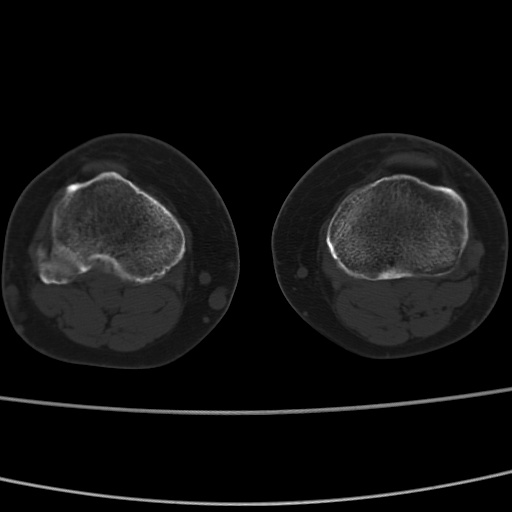

女性,50岁。【请提供患者临床症状体征】

右膝关节退行性改变,关节游离鼠。

右膝关节退行性改变,滑膜黏液囊钙/骨化并游离。

右膝关节退行性改变